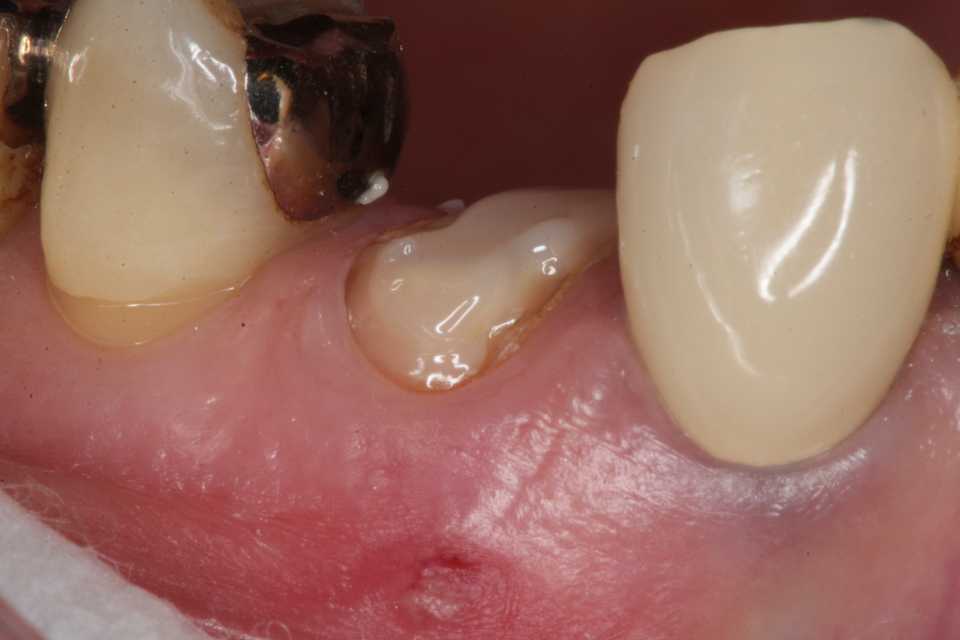

残根上のCR8 2025.10.28